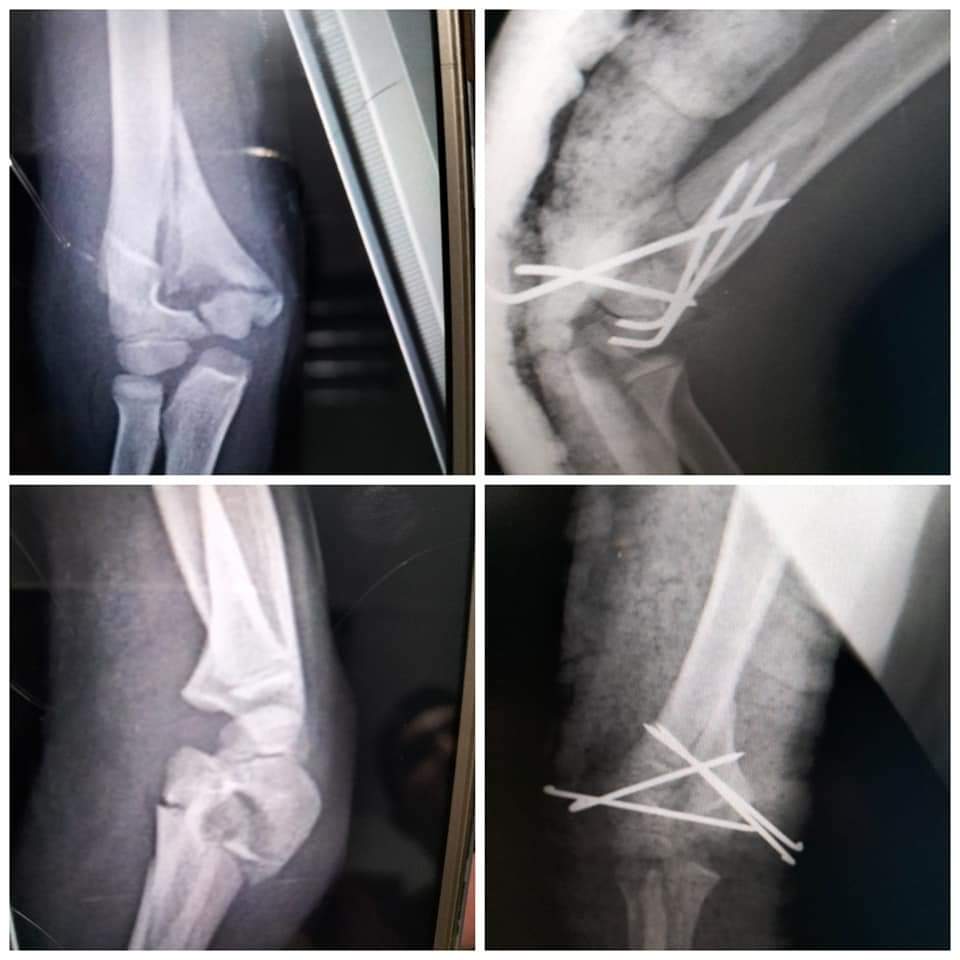

في سياق آخر وتنفيذاً للمبادرة الرئاسية بالقضاء علي قوائم الانتظار الخاصة بالعمليات الجراحية، قام الفريق الطبي بقسم العظام بالمستشفي بإجراء ١٤ عملية جراحية خلال الأسبوع الماضي، وذلك بعد إجراء كافة الفحوصات الطبية والمعملية، والأشعات اللازمة للمرضي، وتنوعت العمليات بين "كبرى، ومتوسطة، وذات مهارة"، لتشمل عملية رد مغلق مع تثبيت كسر مضاعف مفتوح بعظمتي الكعبرة والزند، وعملية رد مغلق مع تثبيت كسر مفتت مفتوح بأعلى النترء البعيد لعظمة العضد، وعملية رد مفتوح مع تثبيت كسر بنهاية عظمة الشظية بالساق بواسطة شريحة ومسامير، وعملية رد مغلق مع تثبيت كسر بمنتصف عظمة القصبة بالساق بمسامير معدنية مرنة، وعملية رد مغلق مع تثبيت كسر بأسفل عظمة الساق بأسلاك معدنية مع رد مفتوح، وتثبيت كسر بأسفل عظمة الشظية، وعملية رد مغلق مع تثبيت بأعلى النتوء البعيد لعظمة العضد، وعملية رد مفتوح مع تثبيت كسر مفتوح مضاعف بعظمة العضد، وعملية رد مغلق مع تثبيت لكسر مفتت مضاعف مفتوح بأسفل عظمة القصبة بالساق بواسطة مثبت خارجي، وعملية إصلاح وتر أكيلس مقطوع كليا، وعملية رد مغلق لخلع متكرر بأصابع القدم، وعملية استخراج جسم غريب من القدم تحت الأشعة المرئية CARM، وعملية تنظيف ورتق وإصلاح جرح متهتك بمنتصف عظمة القصبة بالساق، وعملية رد مغلق مع تثبيت كسر مفتت بالنهاية البعيدة لعظمة الكعبرة....